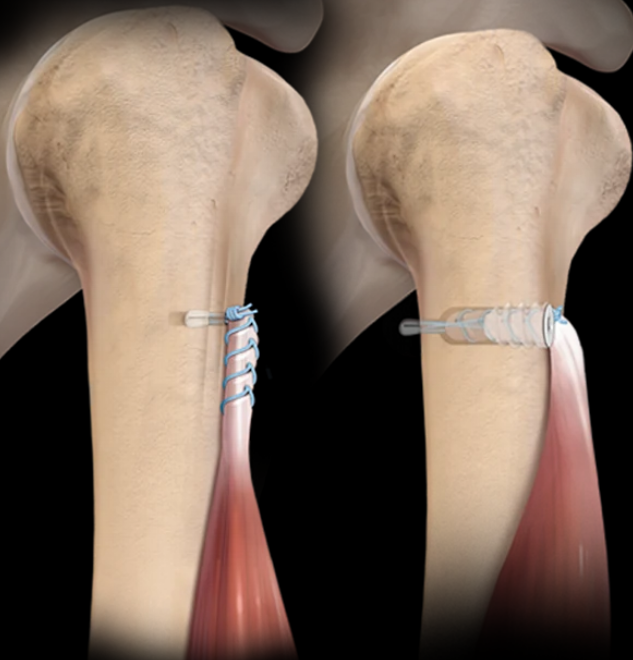

Arthrex Products

Arthrex’s innovative spirit has pioneered the field of arthroscopy and sports medicine and led to the development of more than 1,000 innovative products and procedures each year. Focused on patient safety and clinical outcomes, Arthrex is also leading the way in the fields of orthobiologics and arthroplasty, and is making breakthroughs in the treatment of arthritis. Additionally, we are developing new technologies with potential multispecialty applications.

Shoulder

Shoulder Arthroplasty

Hip